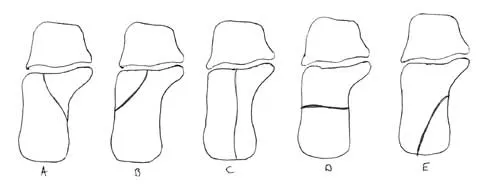

Question 63

In Figure 14, the primary fracture line in a calcaneal fracture is best depicted by which of the following schematics?